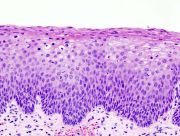

| 2021年7月26日 (一) 18:21 | Cervical intraepithelial neoplasia (3) CIN2.jpg (文件) |  |

85 KB | 77921020 | Uploaded with SimpleBatchUpload | 1 |